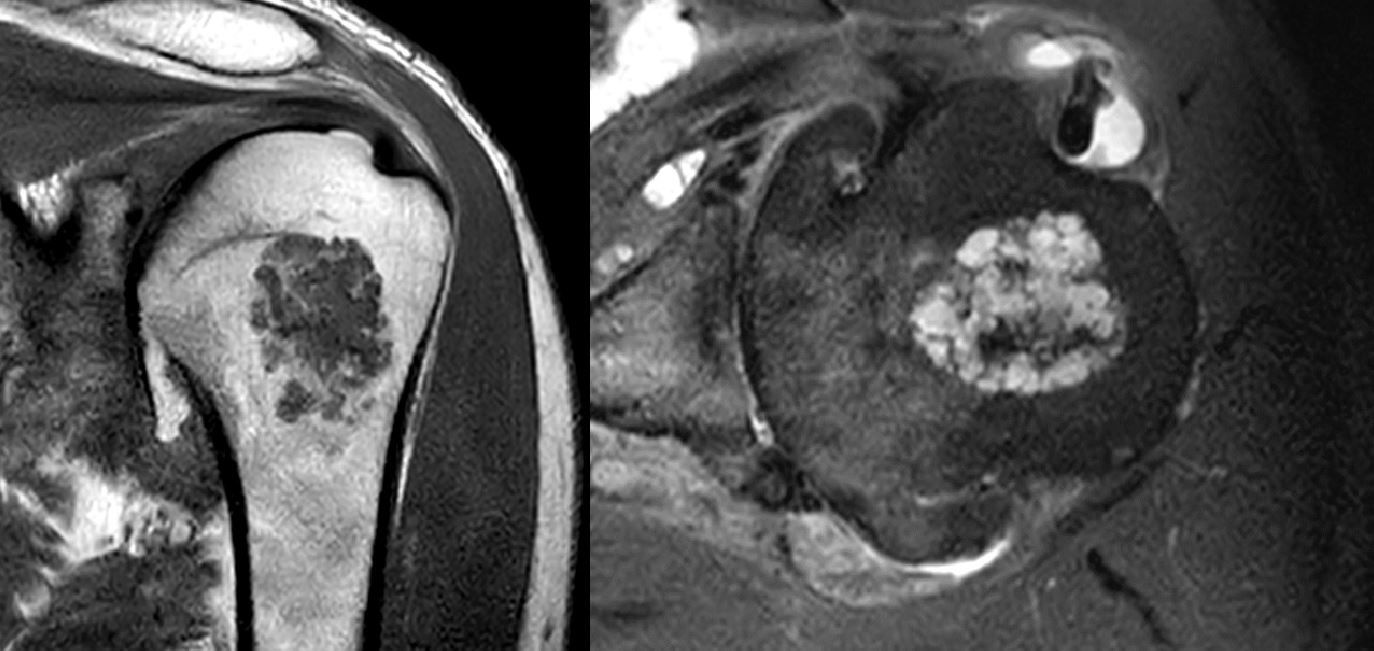

Revolutionising diagnosis and management of cartilage tumours

The musculoskeletal radiology department at BHP member the Royal Orthopaedic Hospital (ROH) has developed a new website designed to enhance the diagnosis and management of cartilage tumours.

bactip.co.uk is a platform that equips healthcare professionals with the tools and knowledge to navigate the complexities of central cartilage tumours. By offering drawings and real case examples, it serves as a valuable resource for interpreting musculoskeletal radiology imaging findings related to these tumours, ensuring their accurate and consistent reporting. Developed collaboratively by experts in the field, bactip.co.uk offers an approach for assessing, diagnosing and monitoring these lesions.

A standout feature of bactip.co.uk is its integrated calculator, which streamlines the grading process based on tumour characteristics, like size and aggressiveness. This innovative tool aims to simplify decision making processes for healthcare professionals dealing with cartilage tumours. This advanced tool also standardises the reporting of central cartilage tumours, reducing subjective differences and improving patient care.

bactip.co.uk enables radiologists and clinicians to make informed decisions by offering an imaging follow up plan. Whether it involves suggesting a referral to an oncology specialist or safely discharging a patient from surveillance monitoring, the protocol provides a detailed framework customised for each unique case.

As a leading authority in orthopaedic excellence, the ROH musculoskeletal radiology department is proud to share its expertise through bactip.co.uk, an open-source free resource.

Dr A. Mark Davies, consultant radiologist at the ROH commented: “This initiative reflects our commitment to openness making sure that healthcare professionals worldwide can access our cutting-edge knowledge and best practices without any barriers. Our dedication to spreading knowledge and best practices aligns with our shared goal of enhancing patient outcomes on a global scale.”